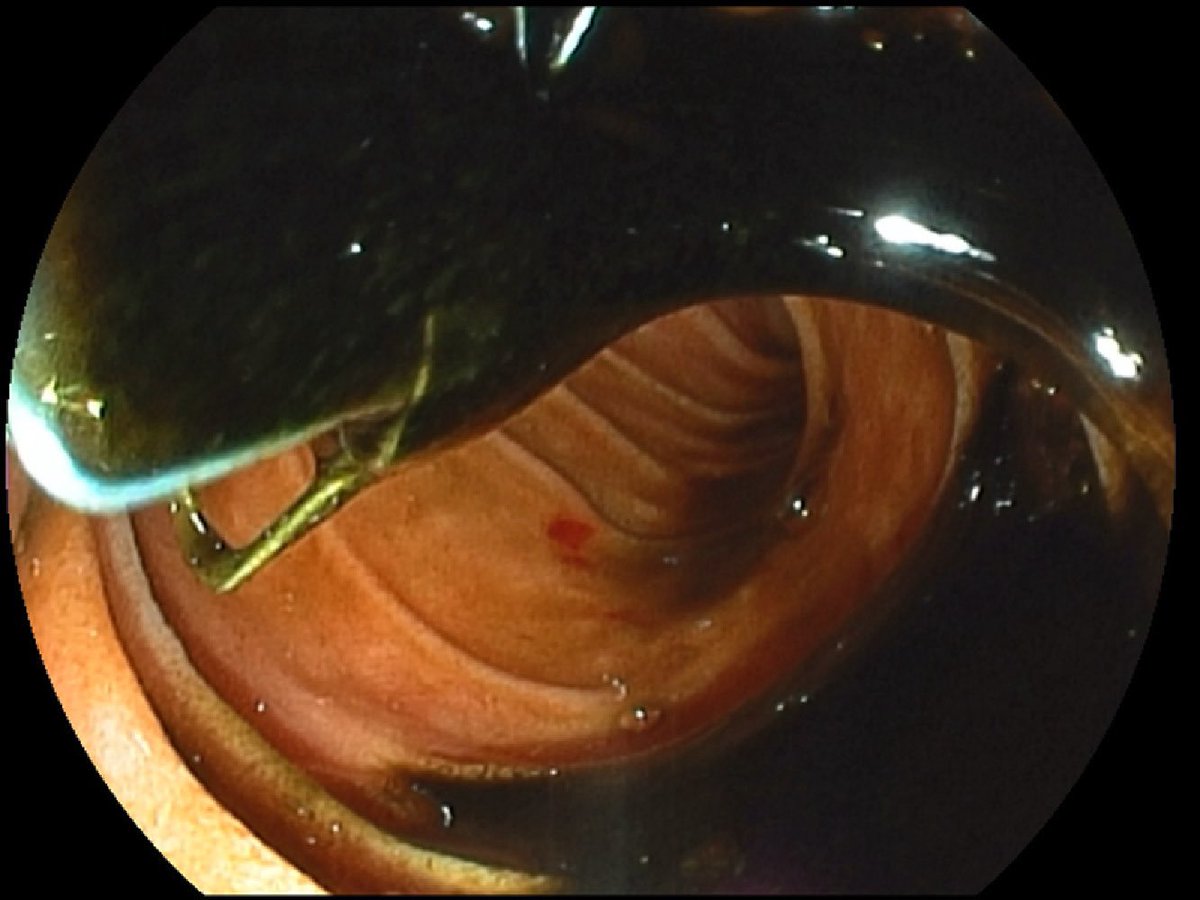

Help: spontaneously perforated duodenum 2 weeks ago managed with a IR Perc drain.

Duodenoscopy this AM revealed a perforated periampullary diverticulum with debris , pus and the drain within it.

Any endoscopic ideas???

#GITwitter @SAGES_Updates